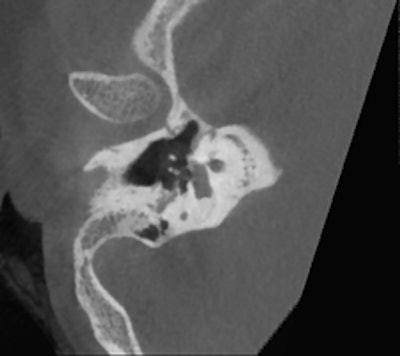

Conebeam CT double oblique reformation of the right temporal bone of a 12-year-old child with conductive hearing loss on the right side, showing a focus of otospongiosis anterior to the footplate. Images courtesy of Dr. Bert De Foer."If the problem is related to conductive hearing loss, then it is most likely to be in the middle ear, in the ossicles, and this requires a CT scan or a conebeam CT. But if the hearing loss is sensorineural, you need to use MRI," stated De Foer, adding that the clinical history of the patient and the clinical examination also will help in choosing the appropriate imaging technique.

He is an advocate of conebeam CT, which is growing in popularity, and recounted the advantages of conebeam CT over conventional CT. He said that he previously conducted all temporal bone imaging on a multidetector-row CT, but he now uses conebeam CT far more frequently. It is different because he uses a flat-panel detector, which provides a high resolution, he explained. Images scan at 0.1-mm resolution, whereas multidetector-row CT scans at 0.5 mm to 0.6 mm.

Several of De Foer's patients were initially scanned on multidetector-row CT and returned postsurgery to receive a conebeam CT. The detail on a conebeam CT is much greater, and the dose is also eight to nine times lower with conebeam in our study of it, he said.

"The level of detail of the ossicular chain is better. For example, the footplate detail is clearer," he said. "The facial nerve running through the middle ear has a bony coverage which is hardly visible on multidetector CT but is very visible on a cone-beam; likewise, the bony covering of the superior semicircular canal, which is important in the Tullio phenomenon."

De Foer also described how conebeam CT is particularly suitable for otosclerosis. This pathology relates to a demineralization of the bone in the inner ear, which prevents the stapes from conducting sound. Conebeam CT shows this in more detail than multidetector-row CT, especially in the evaluation of the footplate.